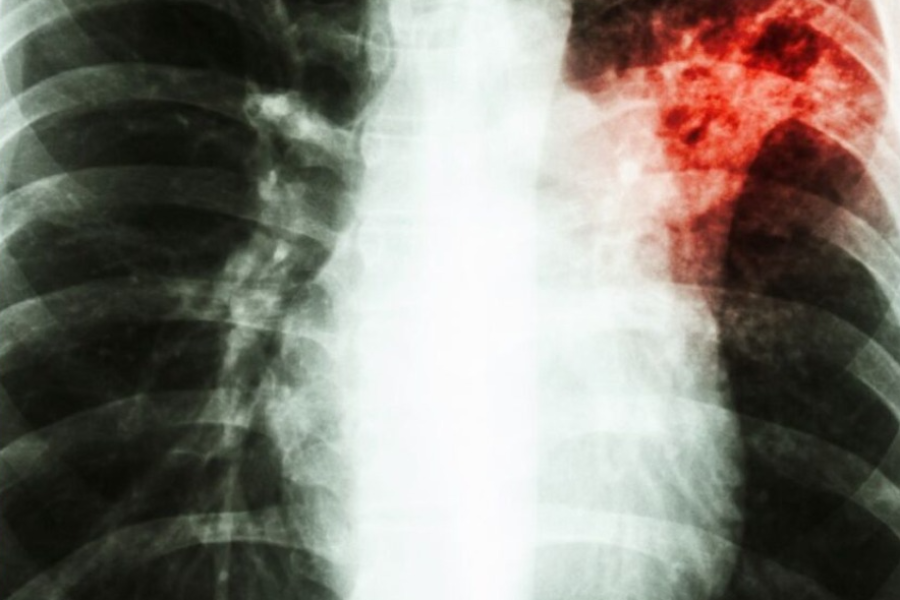

Relação entre diabetes e tuberculose preocupa OMS | Foto: Reprodução/Internet

Segundo dados de 2019 da Organização Mundial da Saúde (OMS), mais de 15% dos casos globais de tuberculose ocorreram em pessoas com diabetes, indicando uma ligação alarmante entre as duas doenças. Este relatório recente destacou a crescente preocupação com a relação entre as condições.

A tuberculose, é uma infecção bacteriana que afeta principalmente os pulmões e tem sido uma das principais causas de morte no mundo, especialmente em países de baixa e média renda. Ao mesmo tempo, o diabetes, que compromete a capacidade do corpo de regular os níveis de açúcar no sangue, está em ascensão global, em parte devido ao aumento do sedentarismo e da má alimentação. Quando combinadas, essas duas condições podem representar sérios riscos à saúde.

Pessoas com diabetes têm três vezes mais chances de desenvolver tuberculose em comparação com pessoas sem a doença. O diabetes enfraquece o sistema imunológico, o que facilita a proliferação da bactéria da TB. Além disso, o tratamento de ambas as doenças pode se tornar mais complicado, pois os medicamentos para tuberculose podem impactar os níveis de glicose no sangue, exigindo ajustes constantes no manejo do diabetes.